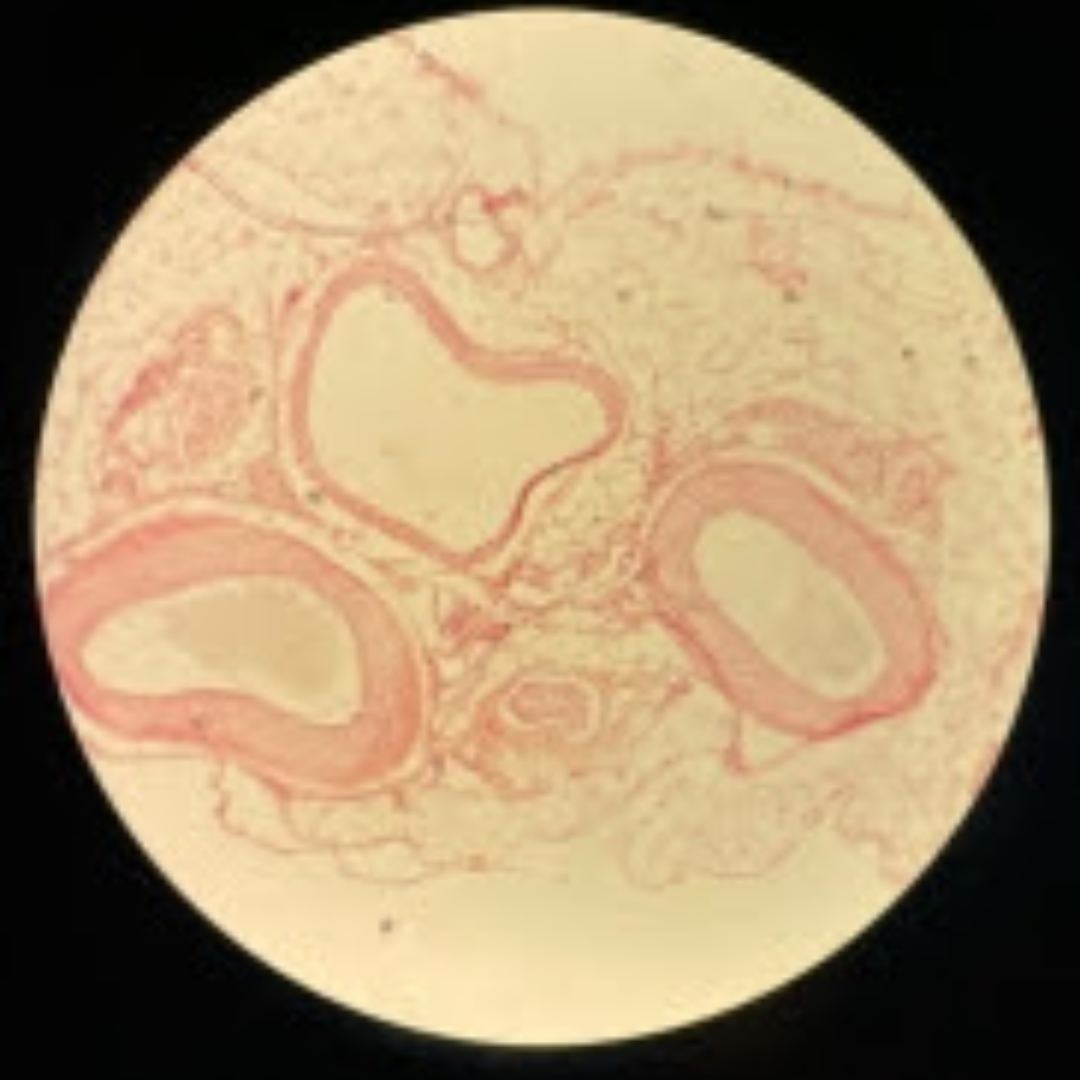

Trachea

Trachea

Trachea

Trachea

Trachea

Trachea

Trachea

Trachea

Trachea